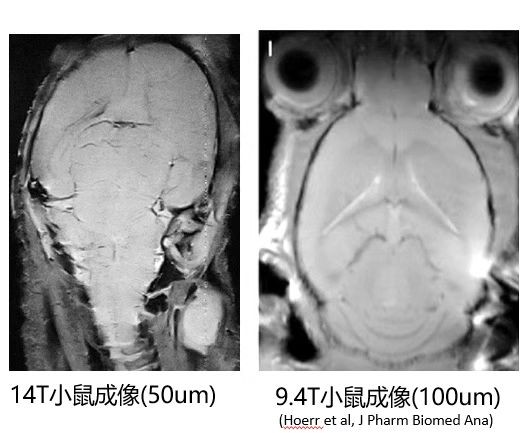

面向前沿科研的顶尖图像质量:凭借14T超高场强带来的信噪比与分辨率的革命性提升,可为脑科学、生命科学等领域提供超高分辨成像能力,为前沿研究提供强大工具。

全脑高清结构成像与图谱构建: 为神经科学家构建更精确的数字化小鼠脑图谱提供数据基础,用于精确定位神经元活动、基因表达区域或病变部位。